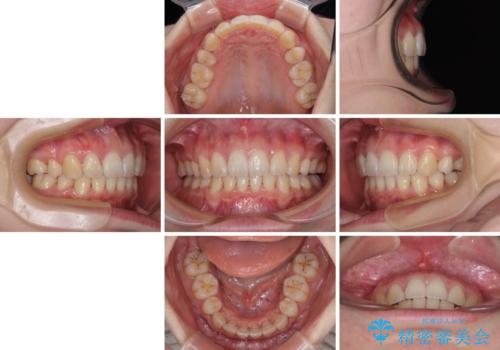

- クリアブラケット

- 1年10ヶ月

順調に治療が進み、2年弱で想定していたとおりの仕上がりにて治療を終えることができました。